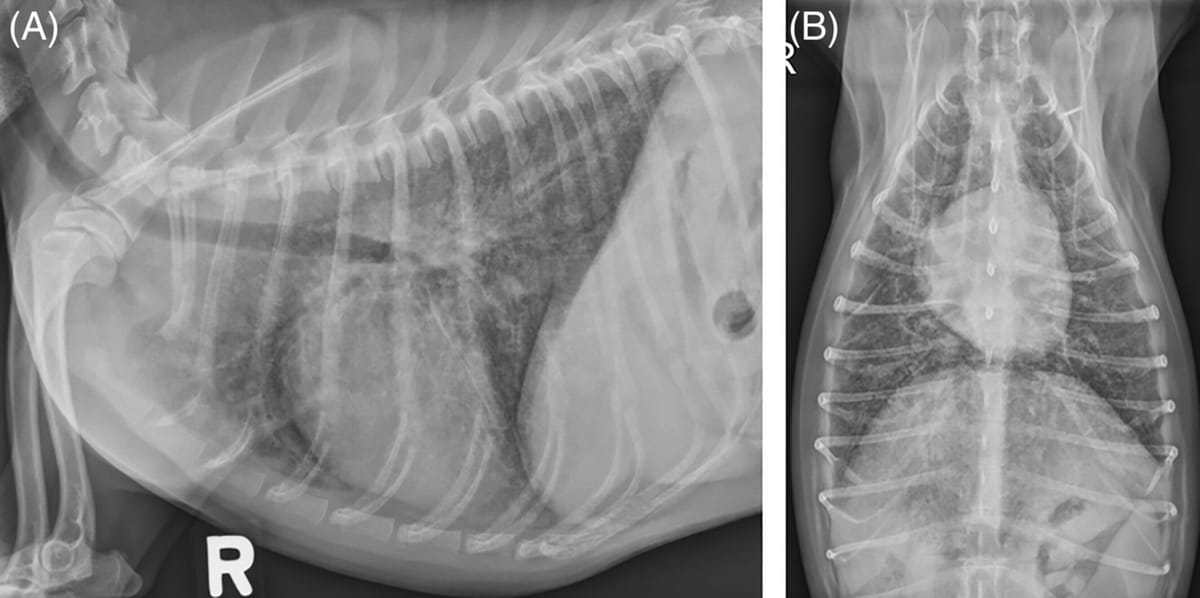

In dog 2, thoracic radiographs identified a diffuse homogenous moderate interstitial pulmonary pattern and increased soft tissue opacity in the perihilar region suspicious for hilar lymphadenopathy.

Right lateral (A) and dorsoventral (B) thoracic radiographs of dog 2 identified a diffuse homogenous moderate interstitial pulmonary pattern and increased soft tissue opacity in the perihilar region suspicious for hilar lymphadenopathy.